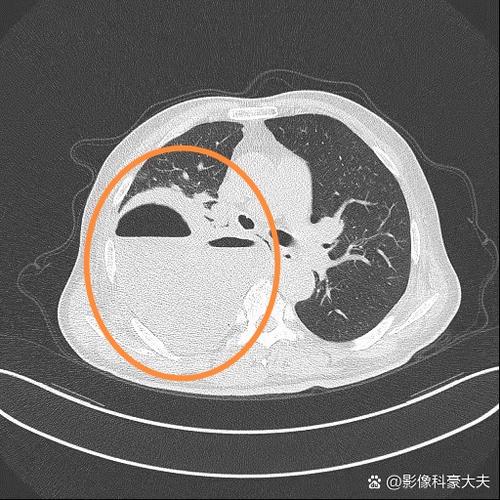

- 影像学改变:胸部CT是确诊的金标准,可以看到肺部有新的炎症浸润影(斑片状阴影)。

(图片来源网络,侵删)- 气道湿化:通过呼吸机或雾化装置,吸入温湿的气体,帮助稀释粘稠的痰液。